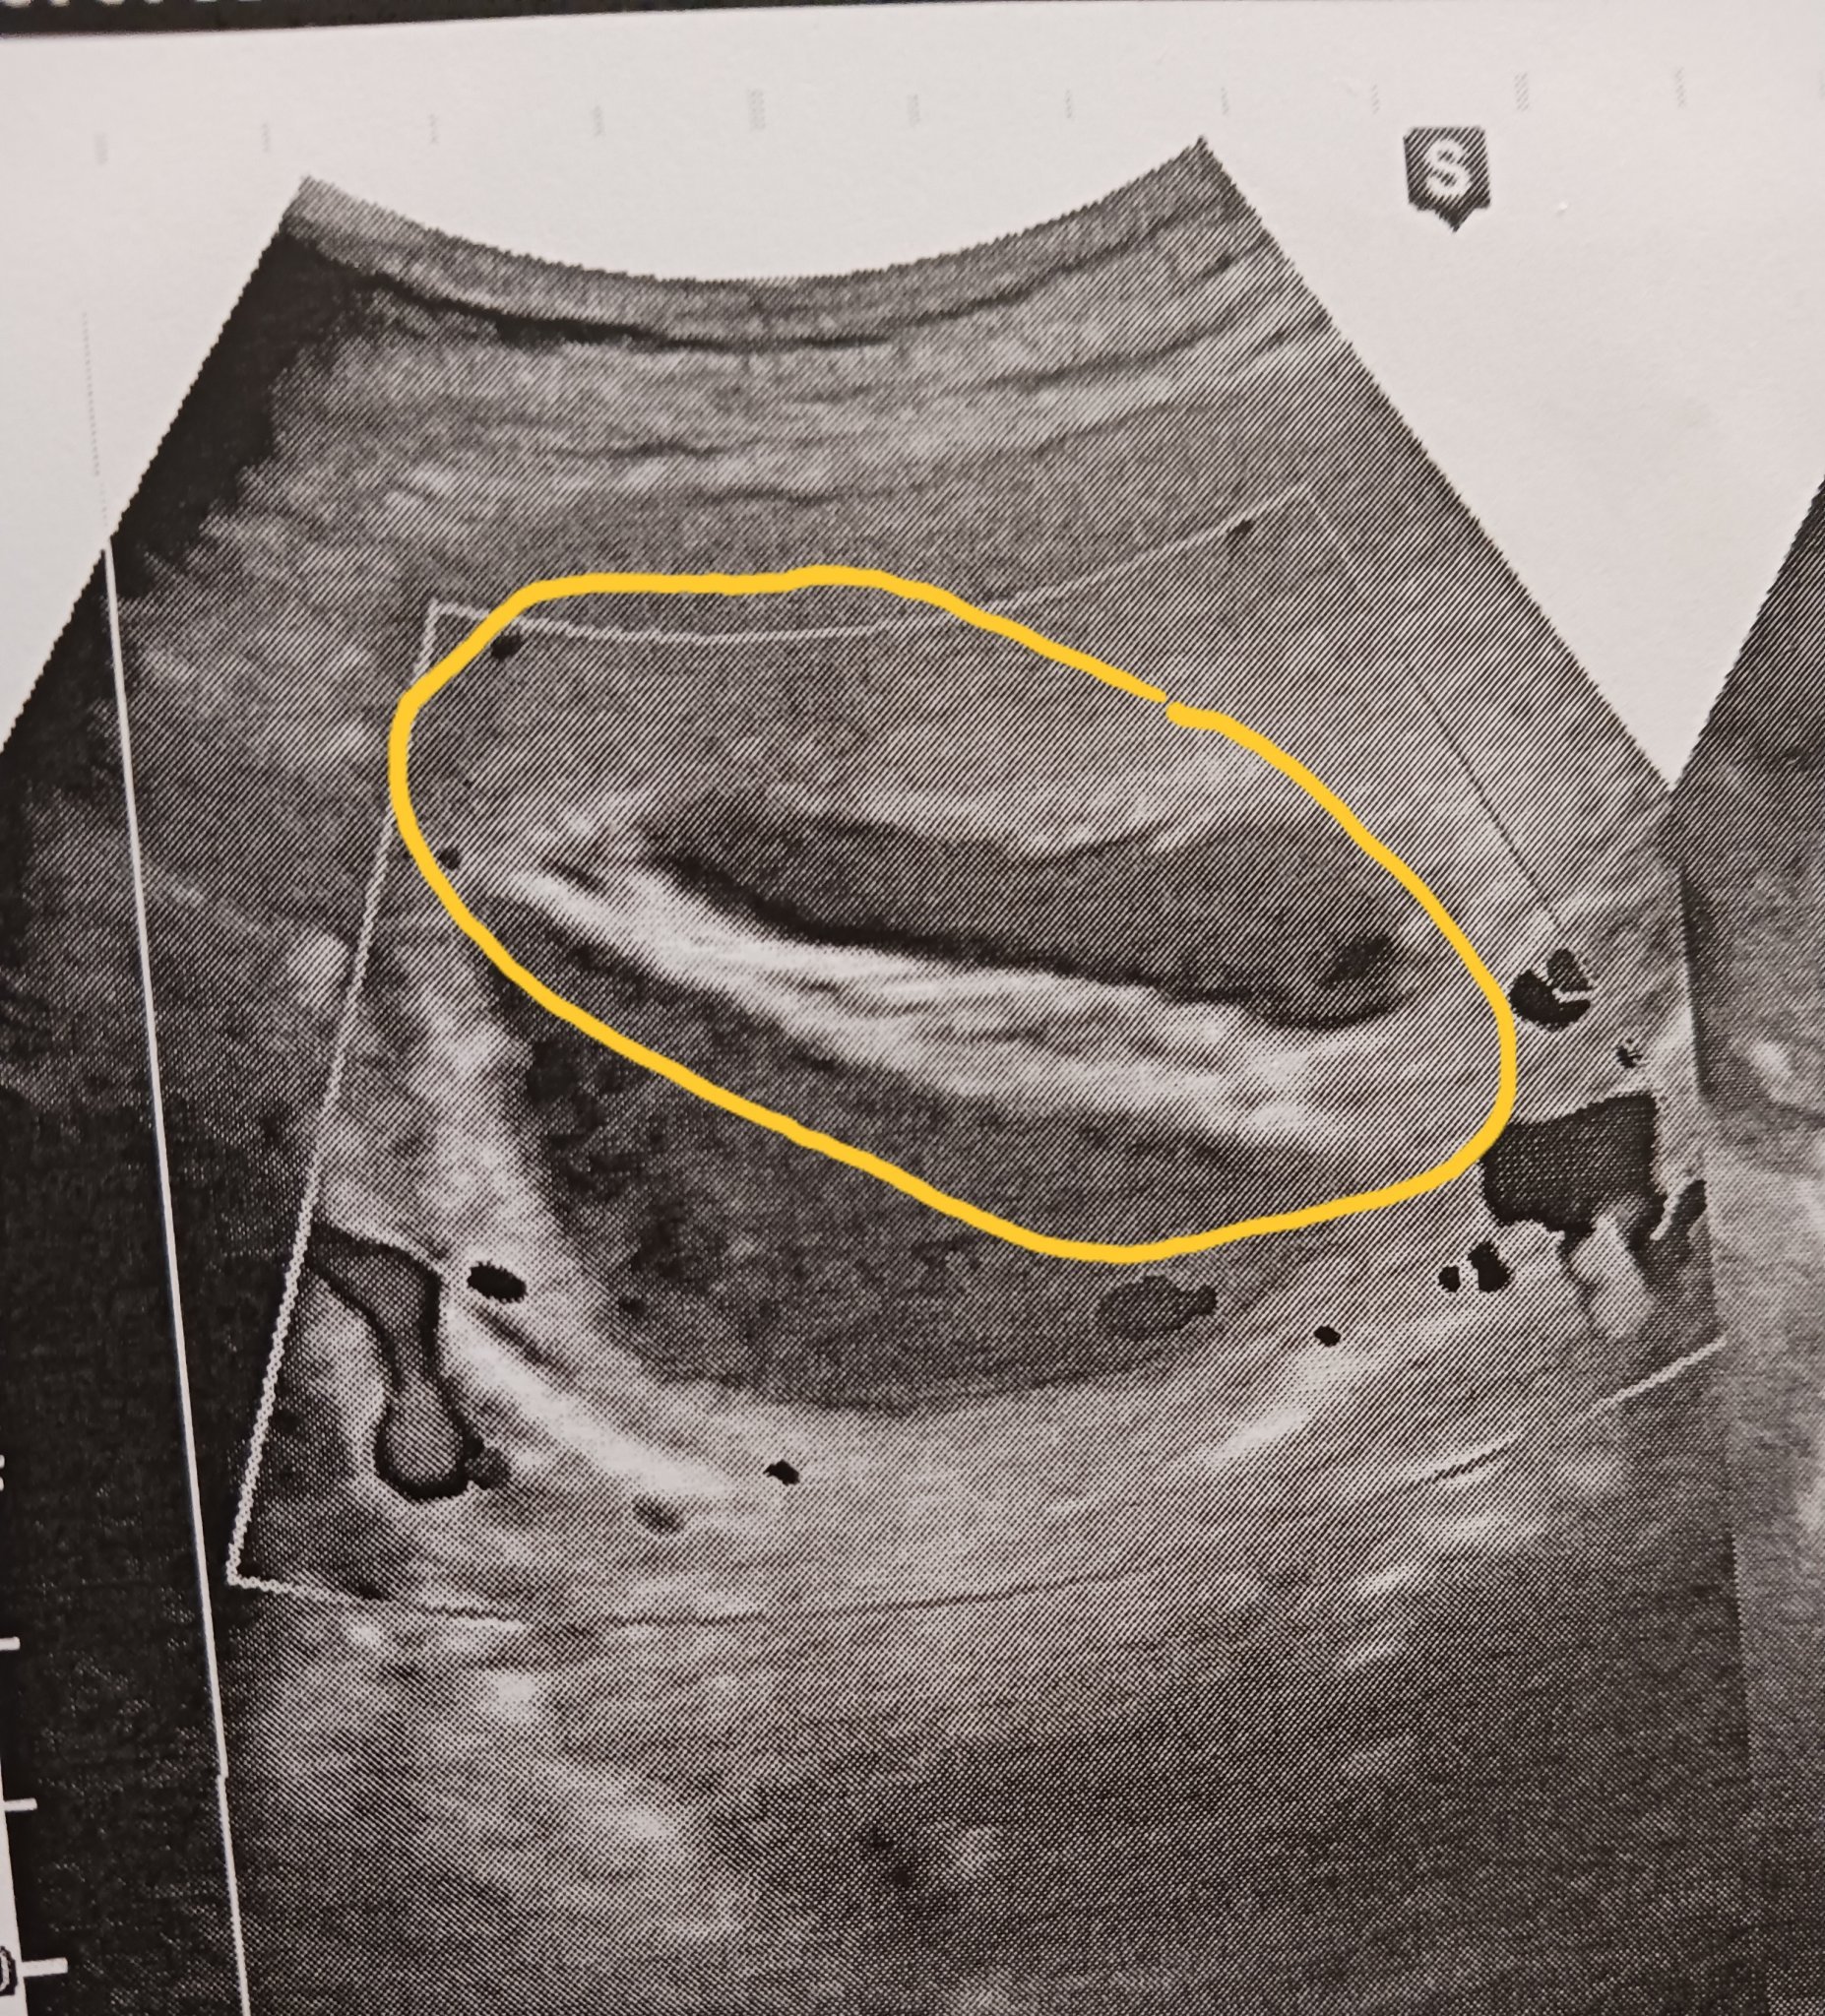

Аг забеляза нещо,което до сега го нямаше и не можа да определи точно какво е . Според нея всичко с плода е наред и не ми вреди, просто ще наблюдаваме,  което ще се случи чак след месец..

Става въпрос за оградено, получава се като втори сак.

Здравейте, аз съм от януарската група, но от скоро чета и вас. Наистина прилича на втори сак. Да не би да са близнаци? 😊 Аз не бих чакала до другия месец, а бих отишла на второ мнение при друг лекар. Успех 😘

Изключи да са близнаци,  по-скоро е тръгнал да се заформя 2ри сак,но празен.

Ще потърся и 2ро мнение😊

Задължително второ и трето мнение ,четвърто,пето...ако видите ,че се чешат по главите и колебаят. Един месец е твърде много време.

Mikmarr, задължително на доктор и то скоро, не искам да те плаша, но може и хематом да е, а тогава трябва да го караш по-внимателно...Имала ли си кървене/зацапване?

Не съм имала нито болки, нито зацапване или кървене , със сигурност ще потърся 2ро мнение..